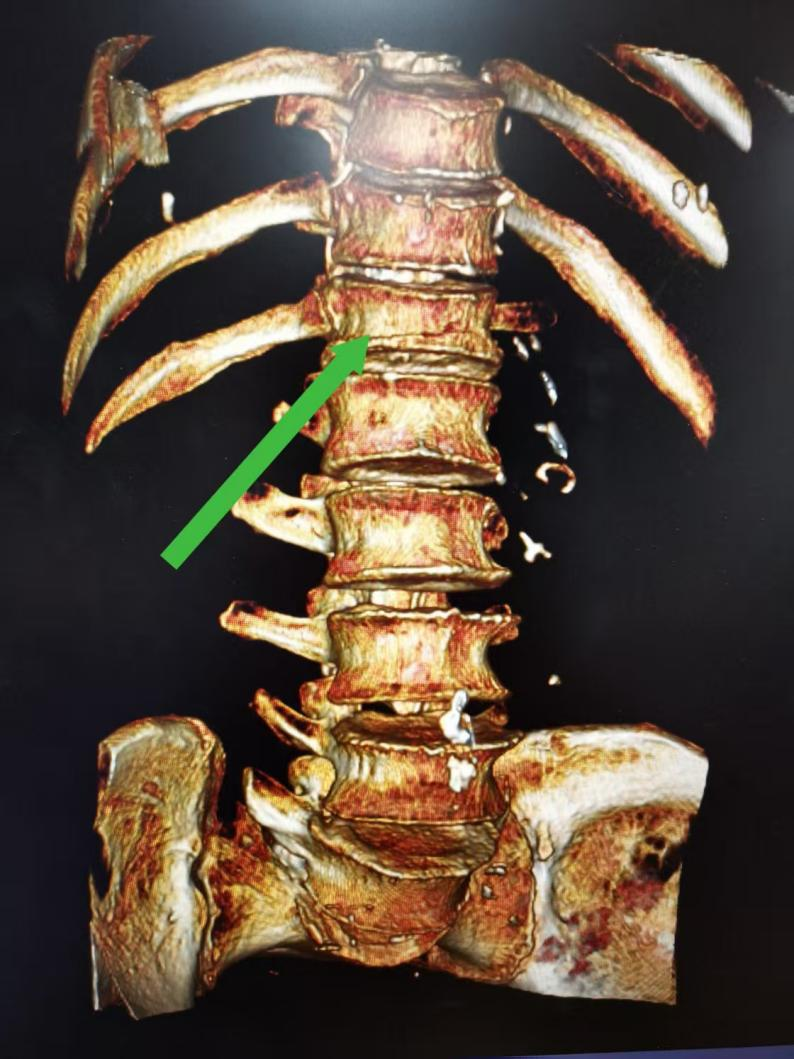

术前CT三维重建显示 第12胸椎压缩骨折(箭头所示)